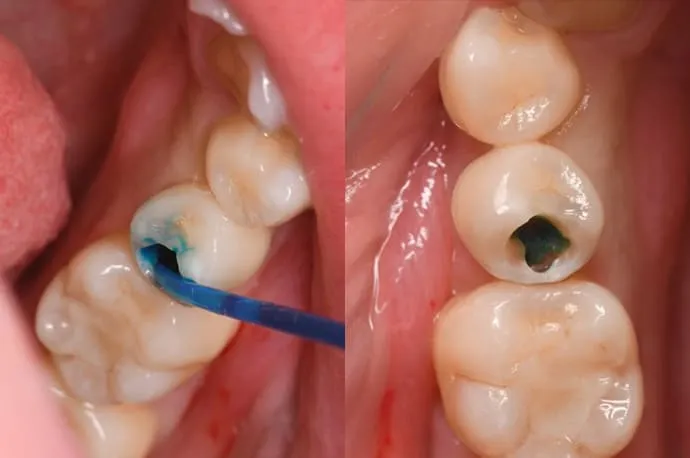

STEP 01

一見すると穴が空いていないように見えますが、内部で虫歯が広がっている状態です。

STEP 02

歯の表層を削ると、中は大きな空洞になっています。

STEP 03

虫歯を染める専用の薬剤を使い、どこまで虫歯が広がっているかを確認します。

STEP 04

染色液で染まった部分を丁寧に除去し、再度染めて確認します。この作業を繰り返し、染まらなくなるまで行います。虫歯は健康な歯に比べて柔らかいため、回転切削器具だけでなく、手作業で少しずつ取り除くこともあります。染色液だけでなく、触ったときの硬さも目安にします。

STEP 05

虫歯の除去が完了すると、かなり大きな空洞になっています。中央の少し青く染まっている部分は、歯の神経が露出している状態です。このように大きな虫歯の場合は、修復の前に根管治療が必要になります。